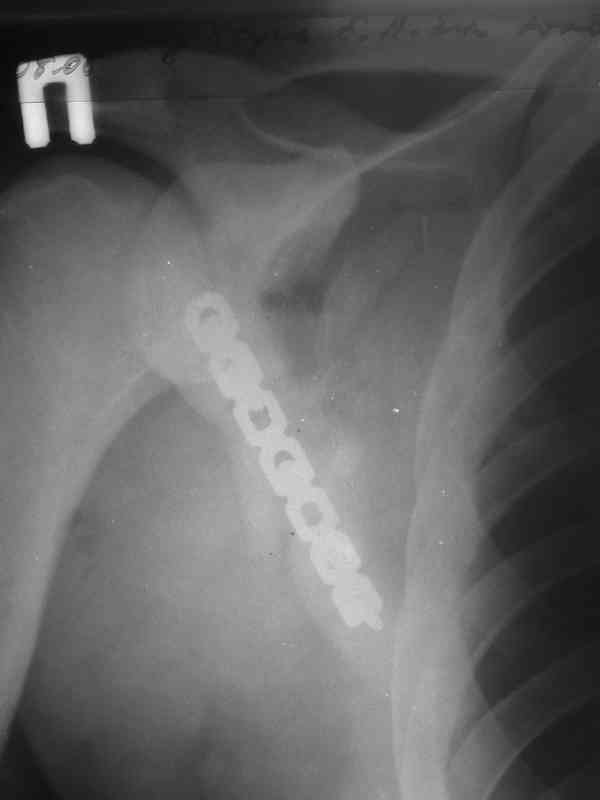

Мы в таких случаях оперируем в 2-а этапа:

1. Стабилизация грудной клетки(фиксируем ребра по одной из линий рекон. LCP)

2. Остеосинтез лопатки из заднего доступа(рекон.LCP, LC-LCP 3,5мм, Т-обр.LCP 3,5мм); ключицу стандартно

К сожелению доктор который занимается грудной клеткой в отпуске, у себя нашёл только вот этот снимок